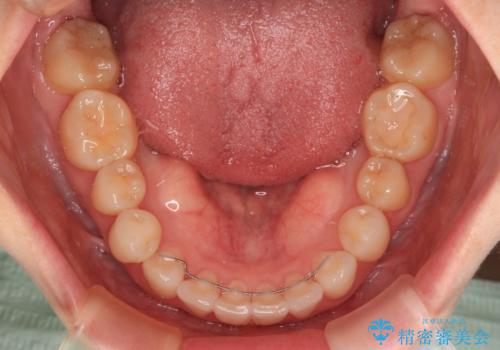

- 前歯のデコボコや八重歯の様になっていることを気にして来院された患者様です。

犬歯捻れて前方に飛び出しており、下顎前歯もそれに沿うようにデコボコとなっていました。

IPR(歯と歯の間を削る処置)によりスペースを獲得して上下顎前歯のデコボコを改善し、前歯が前方に突出しないように設定した上で、インビザラインにて矯正治療を行うこととしました。

途中体調を崩され、長い期間矯正治療を休むことになったため4年半ほどの治療期間がかかりました。